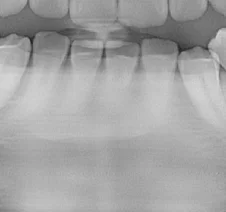

Similarly, with the mandibular anteriors, viewing the original panoramic shows lack of clarity in the apices.